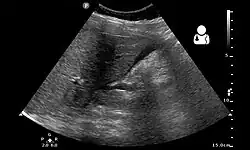

| Ultrasound showing a heterotopic pregnancy (intrauterine + extrauterine pregnancies) with signs that the extrauterine (ectopic) pregnancy has ruptured.[1] | |

The gold standard for diagnosing a heterotopic pregnancy is the transvaginal ultrasound. However, the sensitivity of the transvaginal ultrasound for diagnosing a heterotopic pregnancy has been found to range from 26.3% to 92.4%.[5] Therefore, both clinical symptoms and ultrasound imaging are used to make the diagnosis.